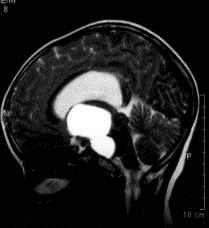

问题 病历摘要:??患者女性,6岁,半年来感觉视力模糊,近10天出现反复头痛,间有恶心呕吐,精神转差,查体:神志清楚,身高90cm,体重25Kg,血压90/55mmHg,右眼视力4.6,左眼视力4.8,双侧视乳头水肿,颈软,伸舌居中,四肢肌张力正常,肌力5级,双侧Babinski征(-)。 手术利用右侧翼点入路,在显微镜下利用鞍区自然间隙进行,一般来说,第二间隙可以窥见的结构有?

选项 A.右侧视神经 B.右侧大脑前动脉 C.前交通动脉 D.垂体上动脉 E.Heubner?回返动脉 F.颈内动脉床突上段 G.基底动脉 H.右侧小脑前下动脉

答案 ADFG

解析 ADFG